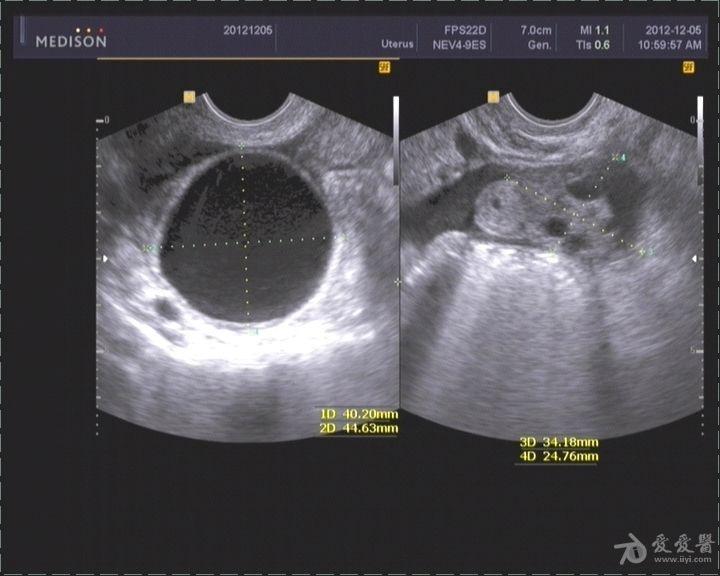

一例典型宫外孕

图片尺寸768x576